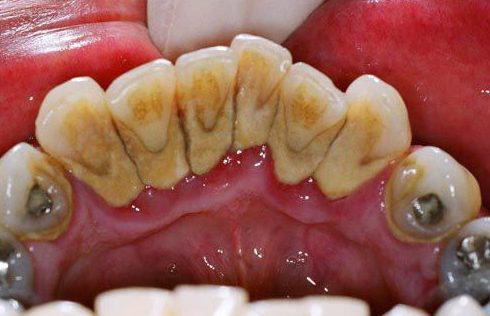

Mảng bám, vụn thức ăn thừa nếu không được vệ sinh sạch sẽ trong thời gian dài sẽ vôi hóa và hình thành nên cao răng bám ở kẽ răng, xung quanh cổ chân răng hoặc dưới nướu răng. Cao răng ban đầu thường có màu trắng đục, vàng nhạt, sau một thời gian có thể chuyển dần thành màu nâu đen, nhất là ở người thường xuyên hút thuốc hoặc sử dụng nhiều thực phẩm đậm màu. Những mảng bám, cao răng này cần được lấy đi để đảm bảo thẩm mỹ và tránh các bệnh lý nghiêm trọng.

Lấy cao răng là gì? Lấy cao răng là quy trình loại bỏ các mảng bám, vôi răng trên thân răng, kẽ răng, dưới nướu bằng thiết bị siêu âm có độ rung phù hợp để chúng bong ra. Nếu không cạo vôi răng định kỳ, bạn có thể bị viêm nướu bởi vôi răng là nơi trú ngụ của vi khuẩn. Chúng có thể tạo mủ, hủy hoại các mô, làm răng lung lay và rụng răng nếu không chữa trị kịp thời.